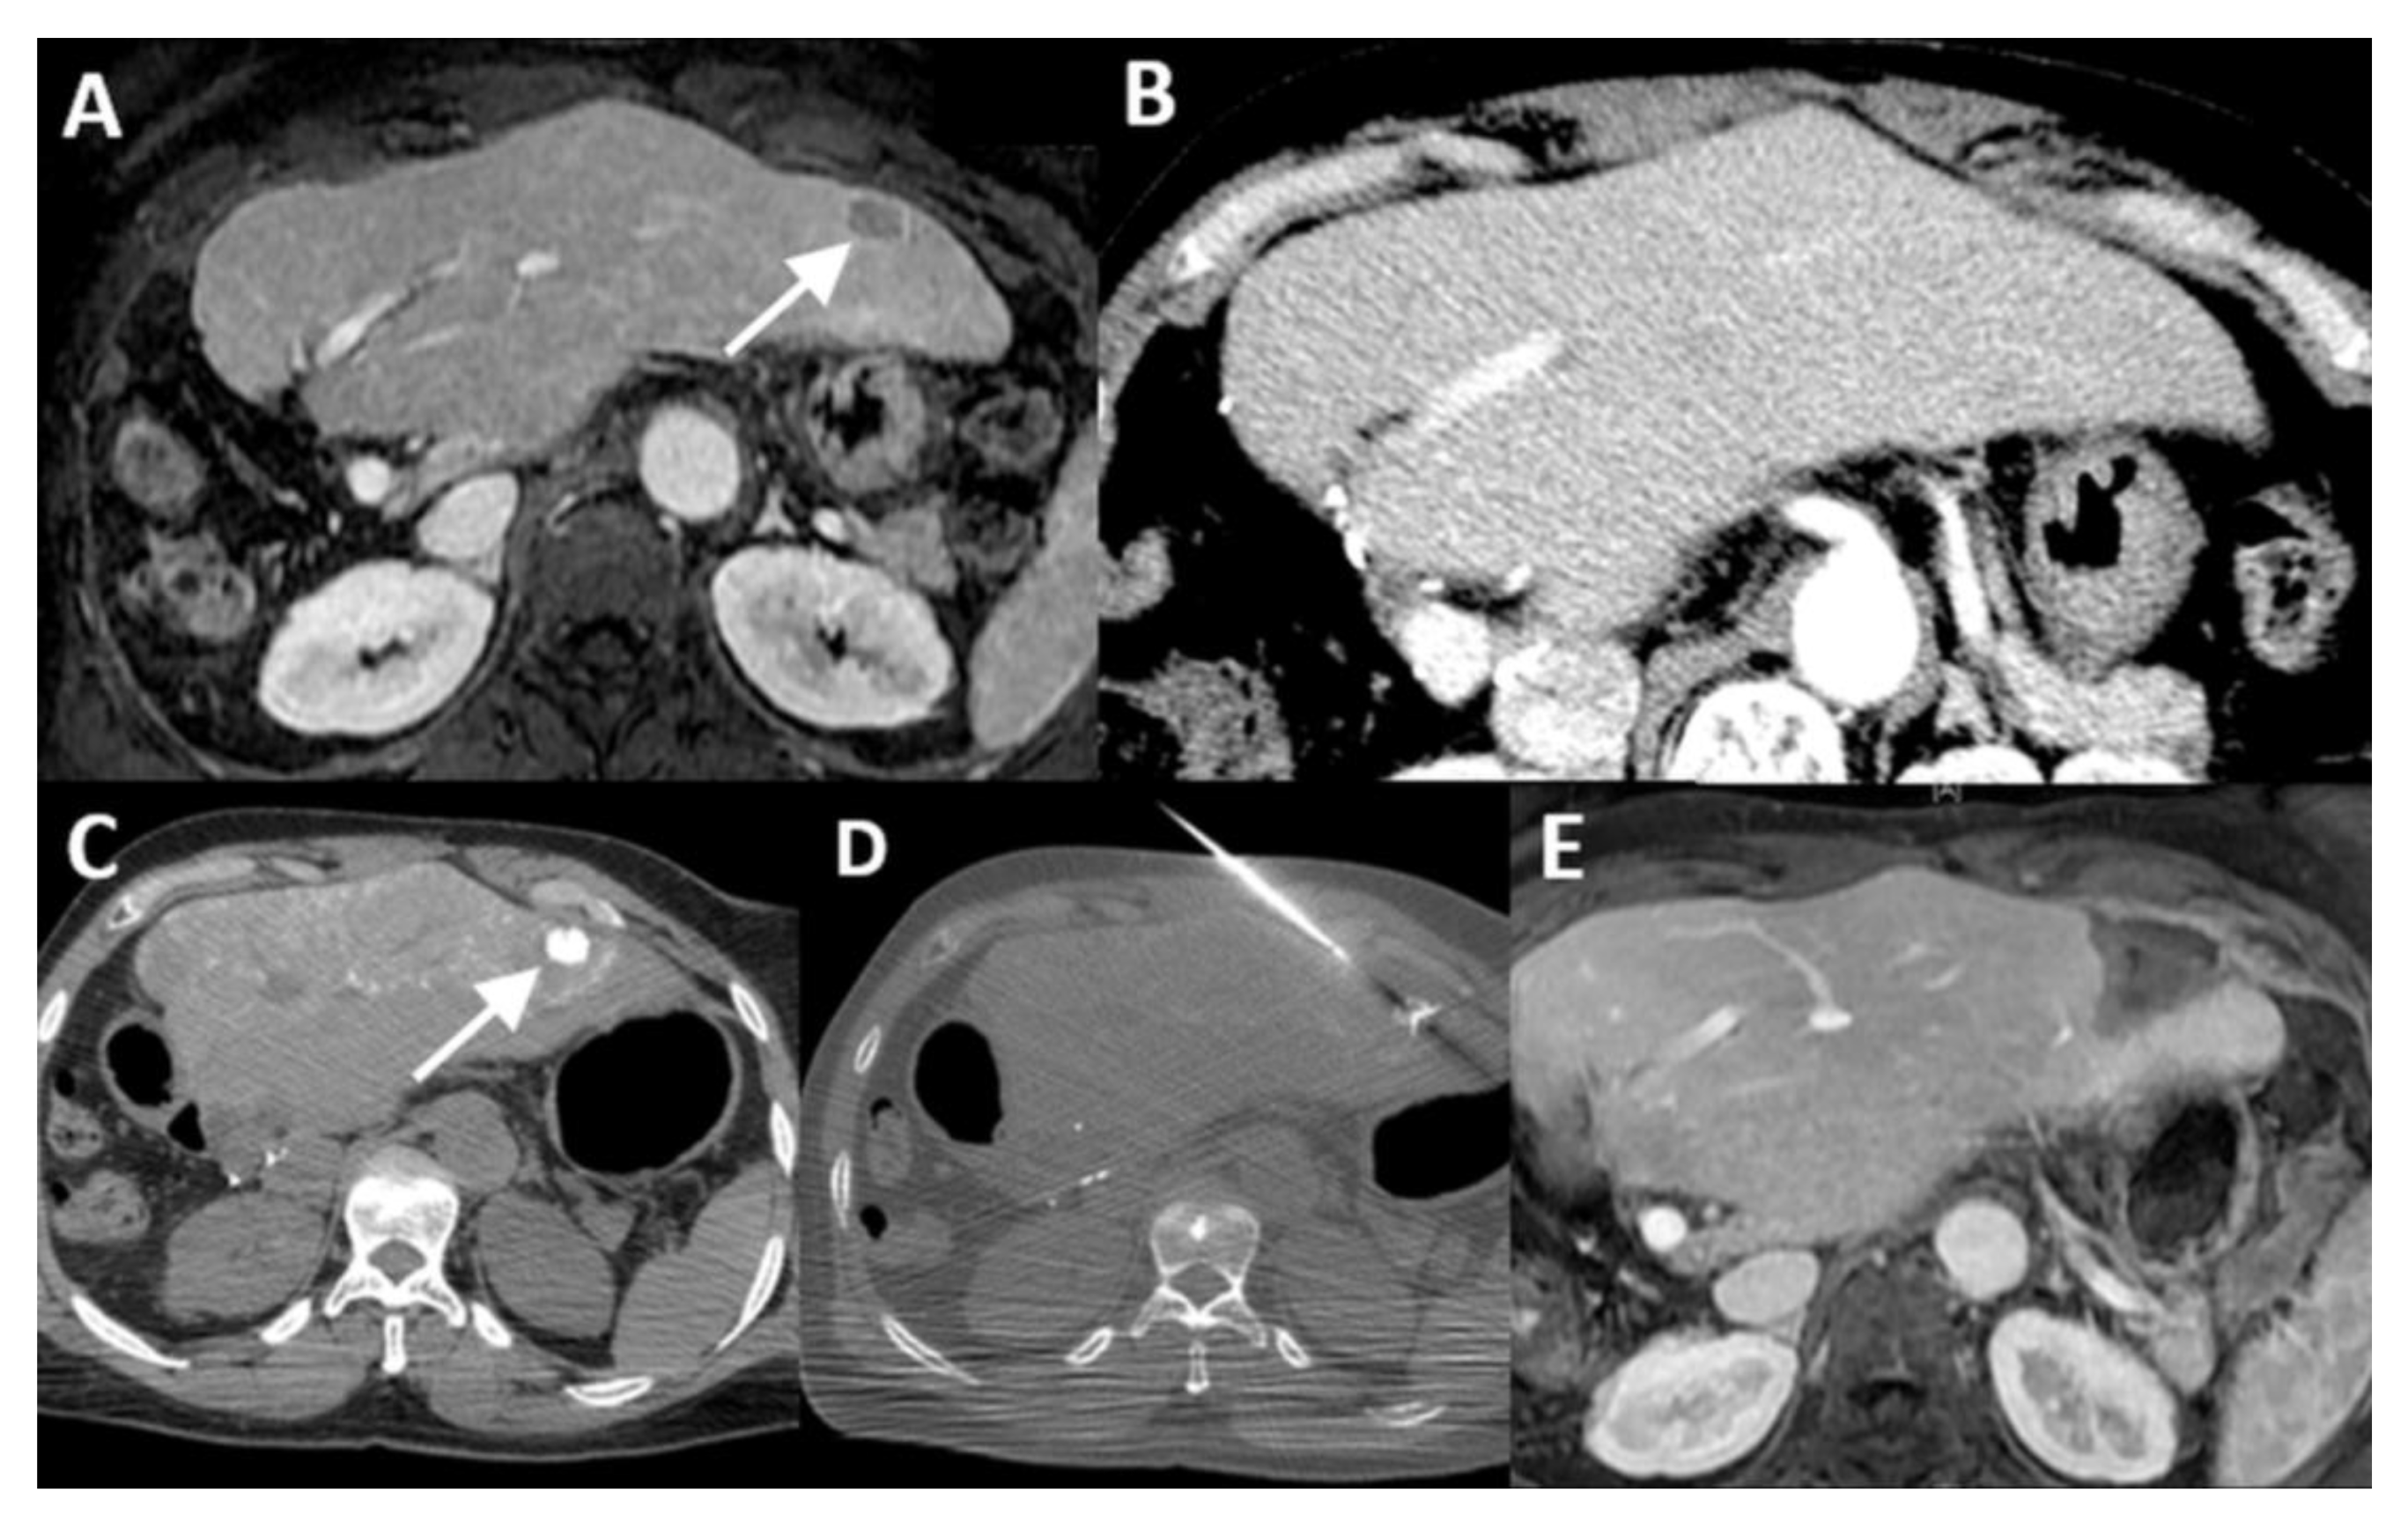

| Case No. | Tumor Size (mm) | Catheter Tip Position | Amount and Type of Contrast per Injection | Ablation Device | Institute |

|---|---|---|---|---|---|

| 1 | 20 mm | Common hepatic artery | 15–20 mL Visipaque™ | Emprint™ Microwave Ablation System, Medtronic-Covidien, Boulder, CO, USA | MD Anderson, Houston, TX, USA |

| 2 | 20 and 7 mm | Common hepatic artery | 4 mL Xenetix 300® | Cool-tip™ RFA Ablation Aystem, Medtronic-Covidien, Boulder, CO, USA | Gustave Roussy, Villejuif, France |

| 3 | 12 mm | Left-sided hepatic artery | Not specified | Cool-tip™ RFA Ablation System | Gustave Roussy |

| 4 | 9 mm | Common hepatic artery | 10 mL Xenetix 300® | Emprint™ Microwave Ablation System | Amsterdam UMC, Amsterdam, The Netherlands |

| 5 | 15 mm | Coeliac trunk | 20 mL Xenetix 300® | Emprint™ Microwave Ablation System | Amsterdam UMC |

| 6 | Not applicable | Common hepatic artery | 20 mL Xenetix 300® | Emprint™ Microwave Ablation System | Amsterdam UMC |

| 7 | Confluent | Common hepatic artery | 10 mL Xenetix 300® | NanoKnife system under ECG-gating; AccuSync model 72, AngioDynamics, Latham, NY, USA | Amsterdam UMC |

| 8 | 15 mm | Common hepatic artery | 15–20 mL Visipaque™ | Emprint™ Microwave Ablation System | MD Anderson |